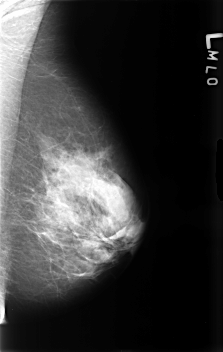

B_3464_1.LEFT_MLO

B_3464_1.LEFT_CC

LEFT_MLO LINES 4568 PIXELS_PER_LINE 2896 BITS_PER_PIXEL 12 RESOLUTION 50 NON_OVERLAY